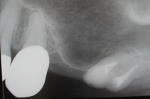

サイナスリフト(骨移植)併用インプラント埋入

ご覧の通り全く骨がないので骨を造りインプラントを埋入しました。

隣の歯も状態が良くなく予後が悪そうです。

抜歯後はインプラントをご希望でしたので、サービスで同部にも骨を移植しておきました。

これで次回オペ時の患者さんの移植のリスクが軽減しました。